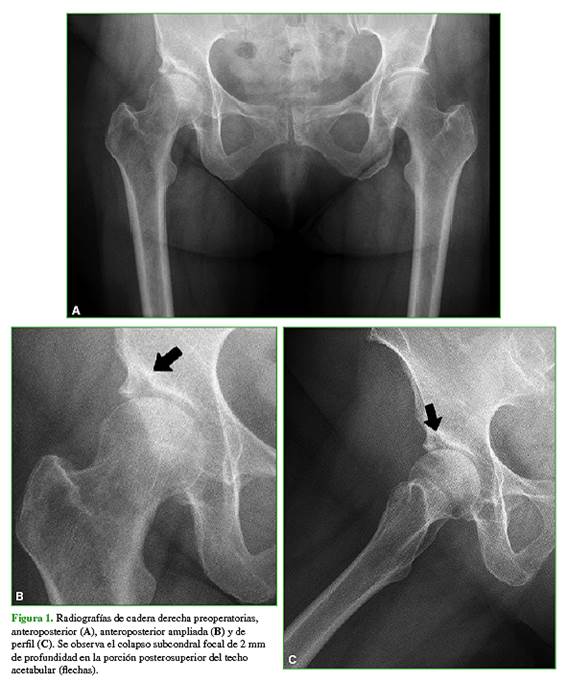

Sobre la base de estos hallazgos, se diagnosticó una fractura por insuficiencia subcondral del acetábulo derecho. En primera instancia y luego de haberle explicado el pronóstico probable, se decidió realizar una infiltración bajo tomografía computarizada con ácido hialurónico y un corticoide de depósito, y se le indicó continuar con descarga de la extremidad afectada mediante un bastón, durante seis semanas. El dolor mejoró levemente luego de tres meses, pero aún continuaba con importantes limitaciones para deambular más de 100 metros. Finalmente, luego de cuatro meses desde la consulta inicial en nuestro centro y ante la progresión de los síntomas, se sometió a una artroplastia total de cadera derecha no cementada (Figura 3). Los controles radiográficos a los tres y seis meses de la cirugía mostraron implantes estables y la paciente había reanudado su actividad habitual sin restricciones (Figura 4).